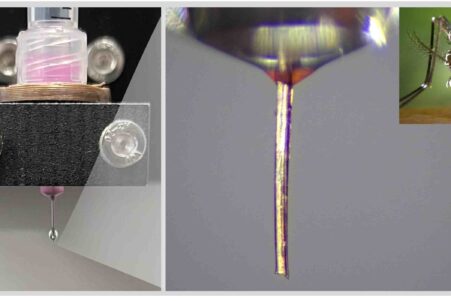

Des chercheurs créent une « éponge » qui absorbe la douleur avant qu’elle n’atteigne le cerveau

Des neurones spécialisés dérivés de cellules souches servant de leurres aux signaux de la douleur.

Des chercheurs créent une « éponge » qui absorbe la douleur avant qu’elle n’atteigne le cerveau

Des neurones spécialisés dérivés de cellules souches servant de leurres aux signaux de la douleur.